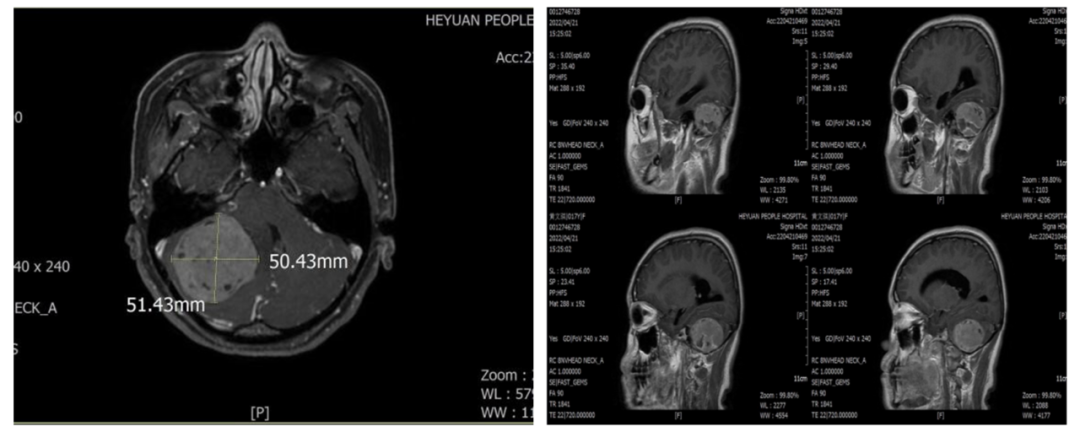

近期,一名中学生患者因突发视力下降就诊于我院,经头颅磁共振检查后发现其颅内有一巨大肿物,约半个拳头大小。

颅脑磁共振

后患者在家属的陪同下到了神经外科一区住院。在做好各项手术前检查后,科主任杨建雄主持召开术前讨论会,杨建雄主任及叶志其主任医师认为:肿瘤位于后颅窝,肿瘤巨大,周围脑组织水肿明显,血供丰富,肿瘤压迫脑干及四脑室,需尽快实施手术切除肿瘤,否则随着肿瘤的增大,患者随时会陷入昏迷,危及生命。术中需仔细操作,防止损伤周围血管、神经,保护好回流静脉,防止术后发生严重的脑水肿,注意保护瘤周正常脑组织。经讨论后,决定采用枕下乙状窦后入路。